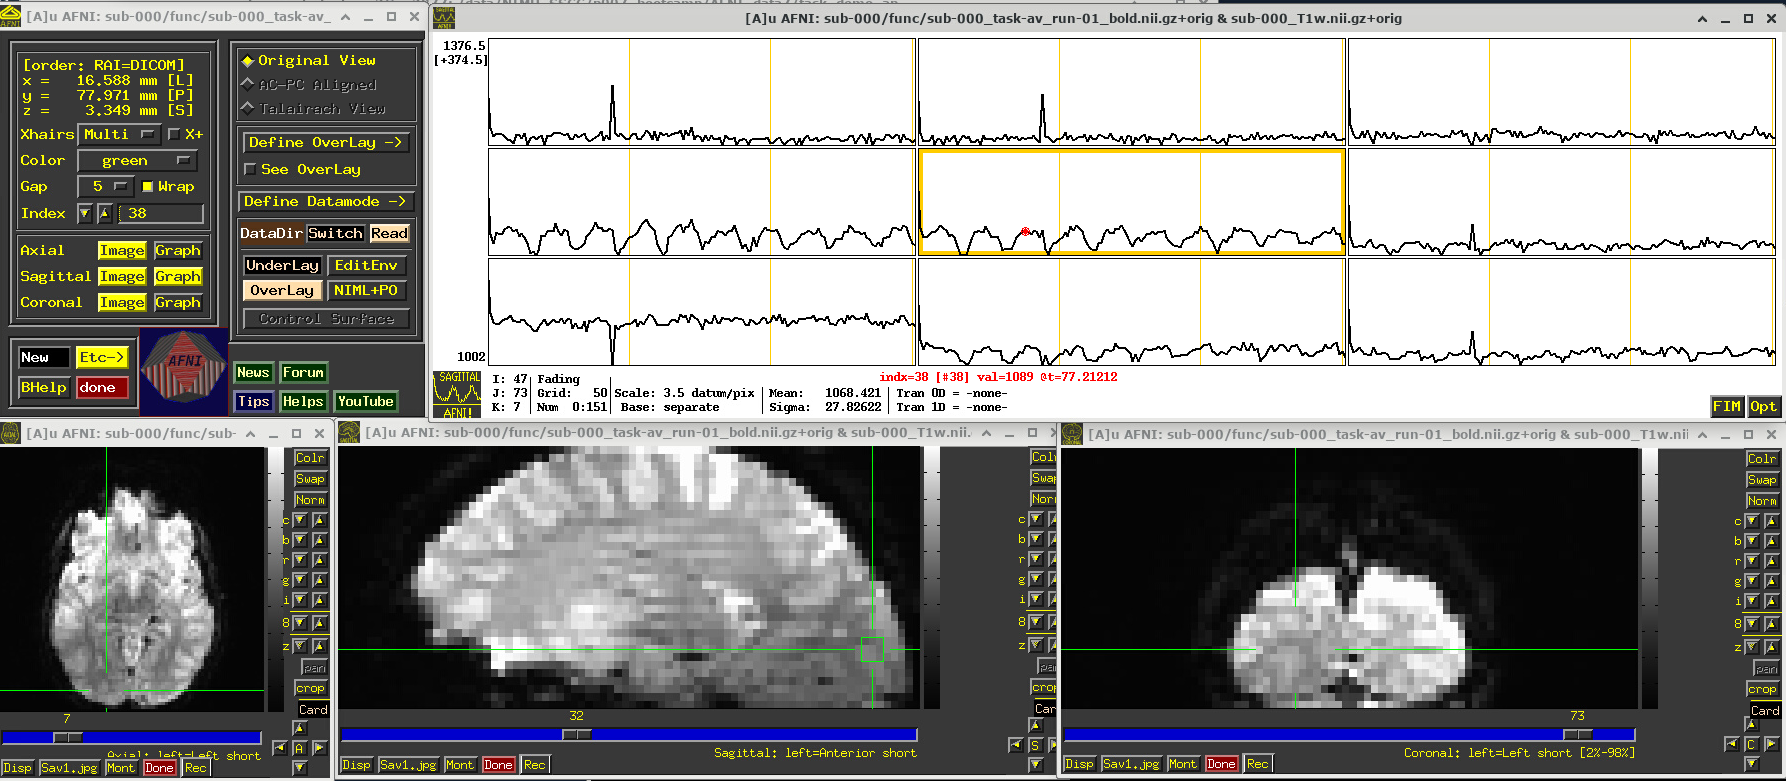

EPI feature: spikes

Click around and see how different parts of the brain appear. For example, if you end up at the location (x,y,z) ~ (8, 31, 60), you will see some spikes that are very big relative to the other fluctuations. These are due to a subject motion event about a quarter of the way through the run.

Some spikes are up, some are down, and some time series don’t appear to have any. This heterogeneity of motion-induced spikiness is one major reason why participant motion is so hard to navigate well in processing and analysis.

Up above, and here as well, you might also notice a subtle thing that appears in all time series at their very start—a different kind of spike. (It is hiding a bit, because of the y-axis there, but look closely.) This one is different because it is always upwards, uniformly. This has a different root cause. Each dataset looks normal there as a 3D volume, but in fact the recorded values are uniformly higher in the first few volumes than the rest—this is a “pre-steady state” phenomenon. It occurs generally in FMRI as the acquisition sequence settles into a steady state. Some scanners or initial data-streams clip out these time points, while others don’t. It is good to be aware that these can occur.

You can tell afni_proc.py to remove the first few EPI volumes, if the input data does include such pre-steady state volumes. And afni_proc.py will automatically check and warn you if it appears that the user did not account for some pre-steady state volumes that appear to be present. (And we note that participant motion can occur in the first few volumes, so sometimes it is hard to tell which affect might be happening, or if both are.) In any case, you need to make sure that your task-based timing files stay synchronous with the EPI datasets as processed!

# Display a screenshot of the AFNI GUI with the first EPI run loaded, checking out spikes

IPython.display.Image(filename='example_snapshots/img_02_afnigui_epi_r01_spikes.png')

../_images/46131ddfd698370db628152f22b5707ca1f78f9b0515788c32fe949500047e05.png